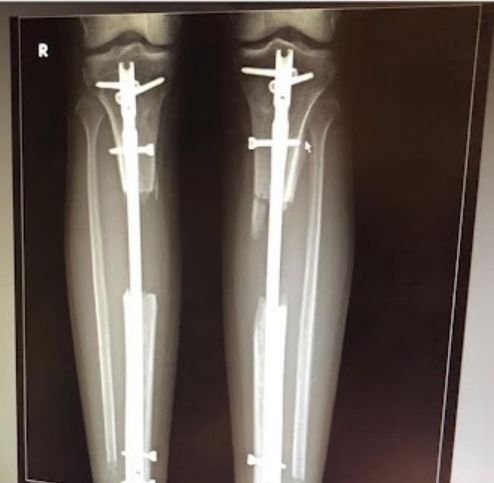

Gallery